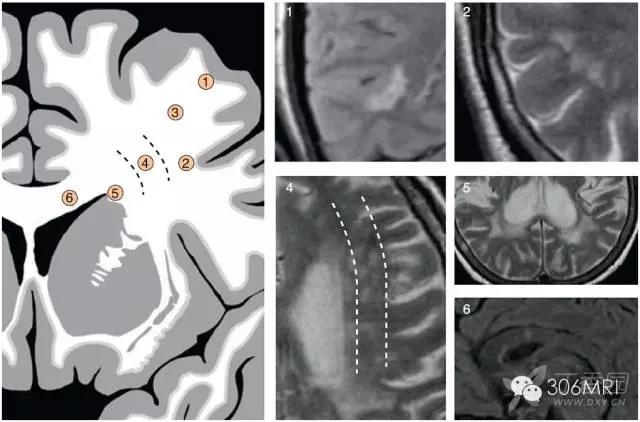

脑白质高信号

脑白质病变的影像学鉴别诊断

深部脑室旁白质高信号是什么意思

脑白质疏松症的诊断和鉴别诊断

脑白质区内mri斑点状异常信号解读

正确解读磁共振脑白质区内斑点影